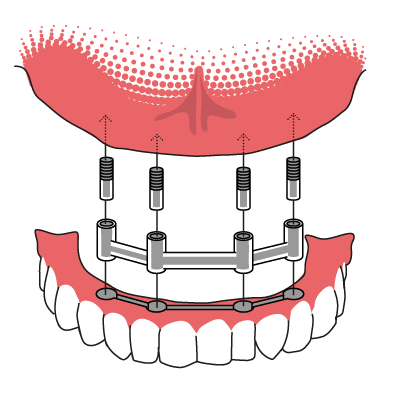

Stegprothese